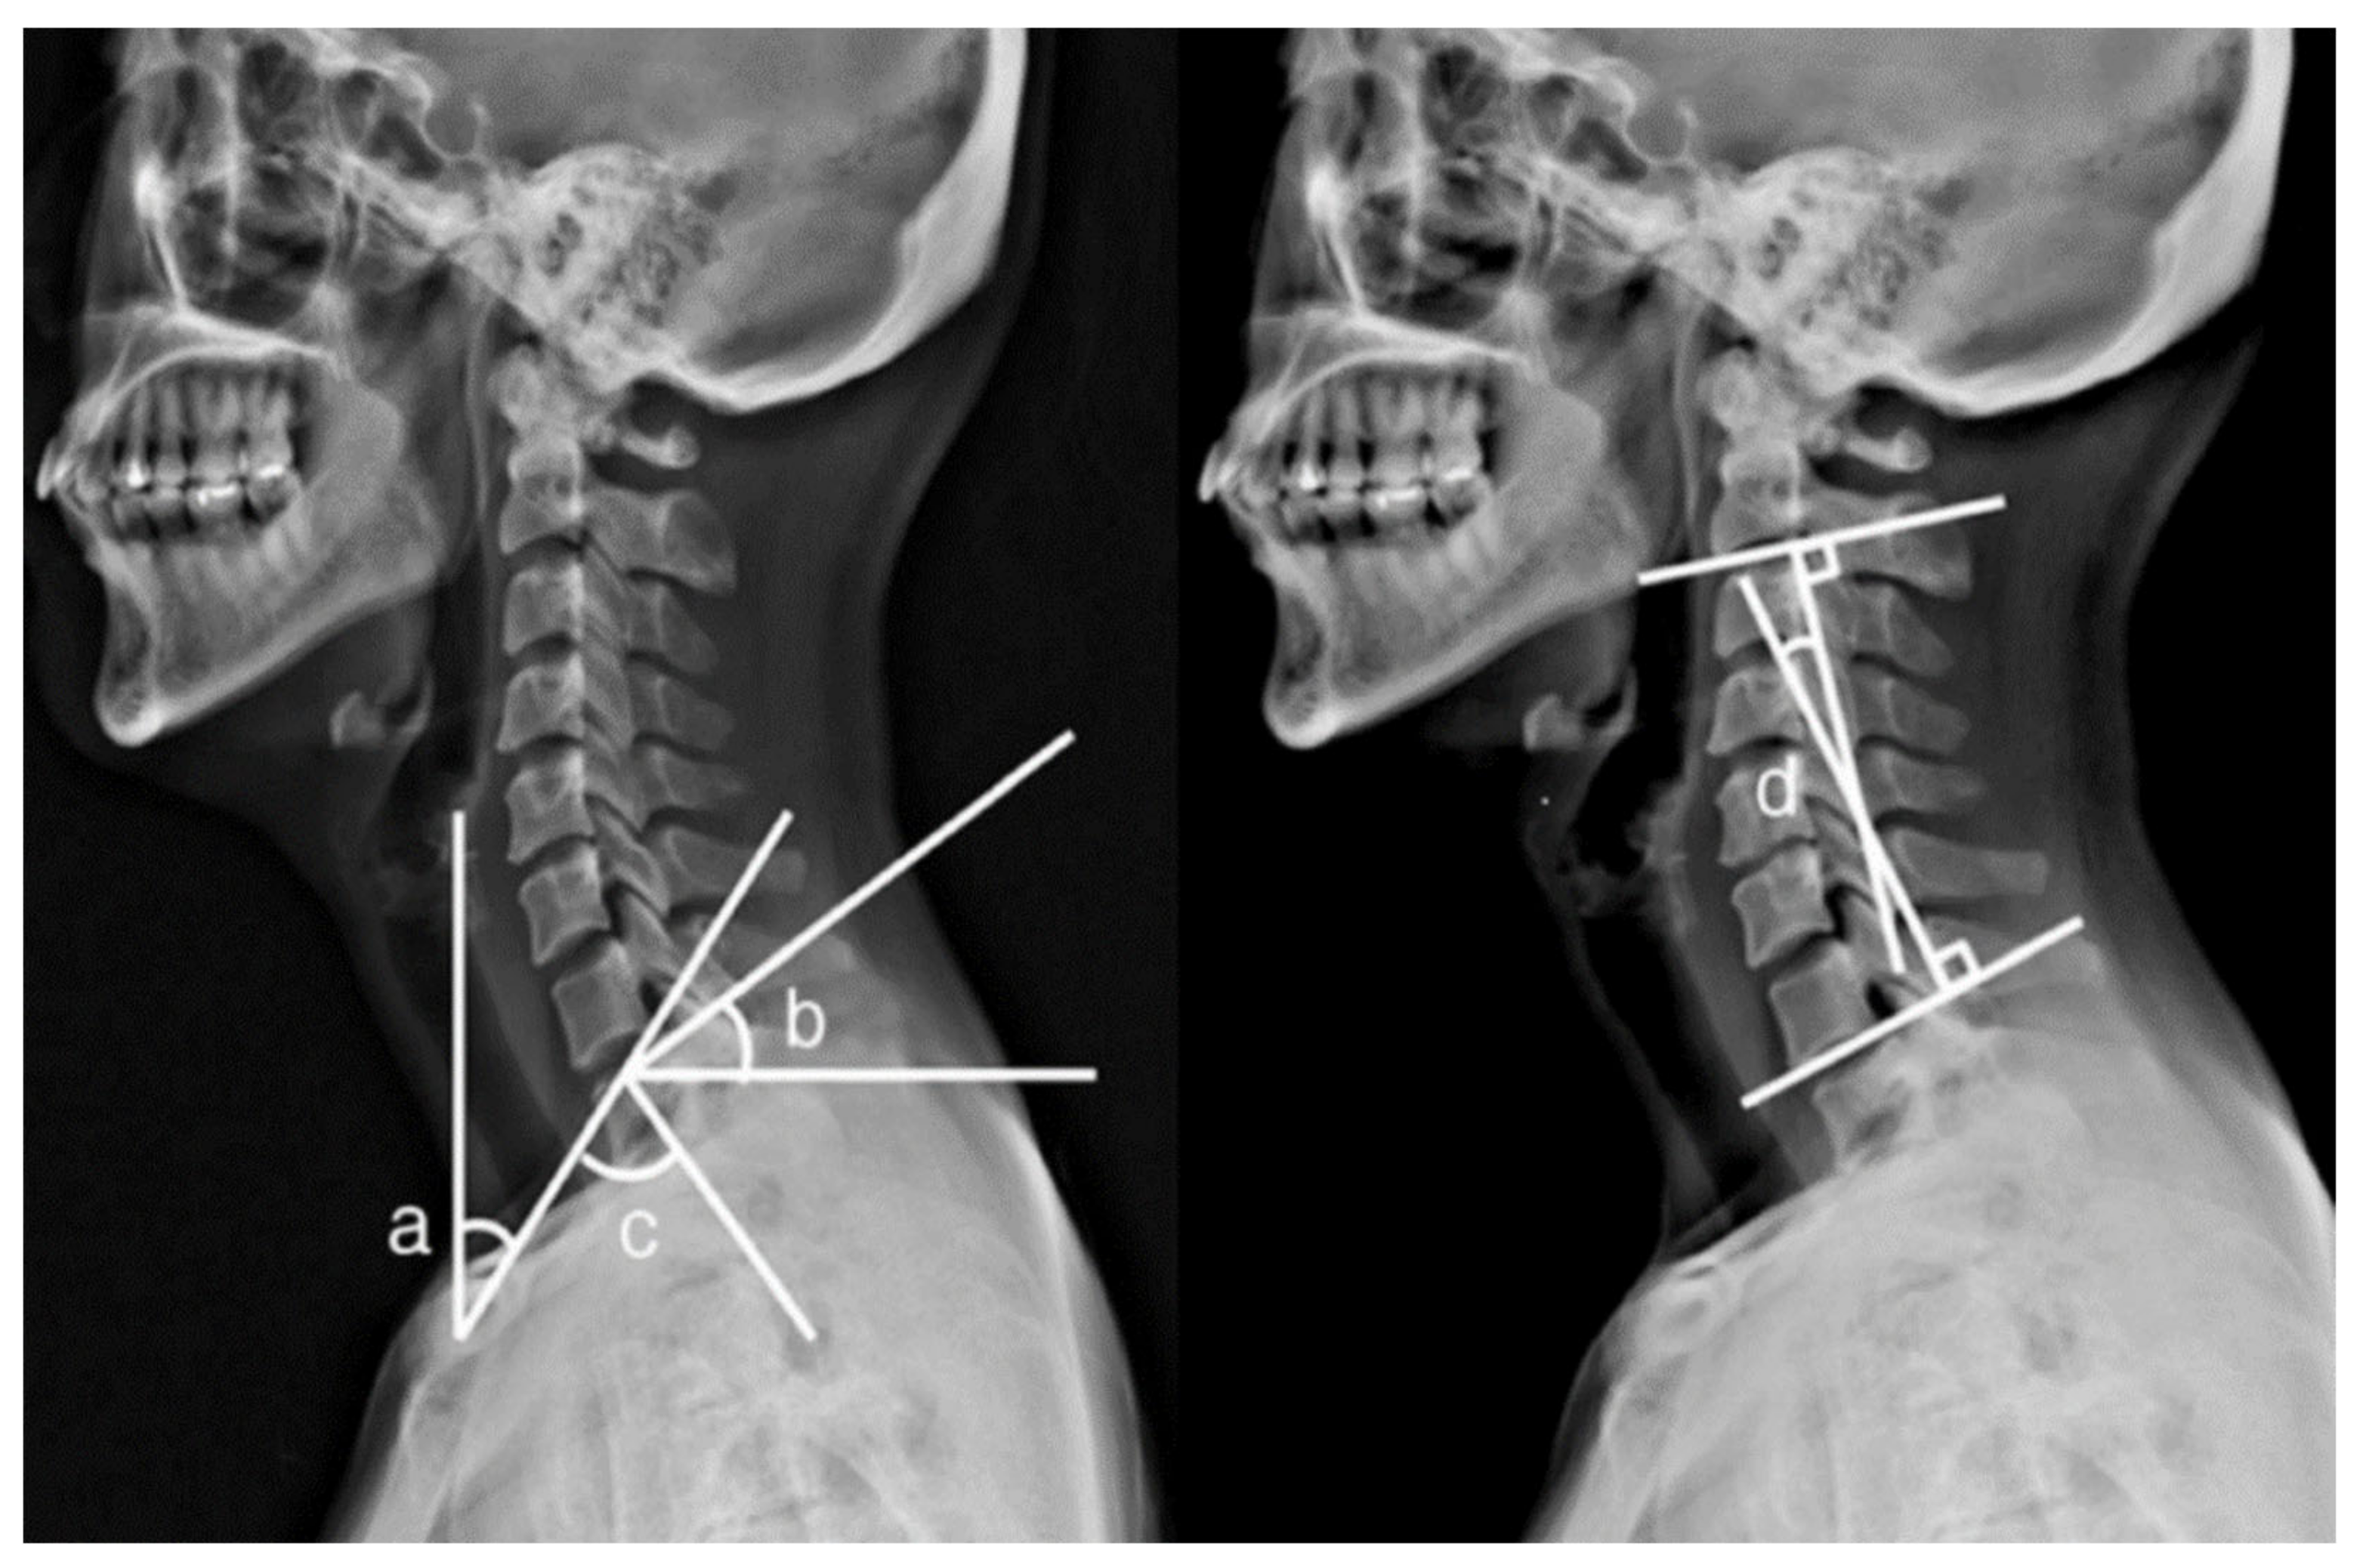

| Kim et al. (2015) [20] | Parameters of Cervicothoracic Spine Segments | Radiographs | NA | All participants were asked to try three pillows of different heights (0, 10, 20 cm). | The thoracic inlet angle (TIA), T1 slope (T1S), neck tilt (NT), and C2-7 Cobb’s angle. |

| Kim et al. (2015) [20] | Crossover design | To investigate the effect of different pillow heights on the slope of the cervicothoracic spine segments. | As the height of the pillow increased, the T1S and C2-7 Cobb’s angle increased, while the NT values tended to decrease. The TIA values, however, remained constant. The 10 cm is recommended as the most suitable pillow height to maintain the physiological curvature of cervical spine. |